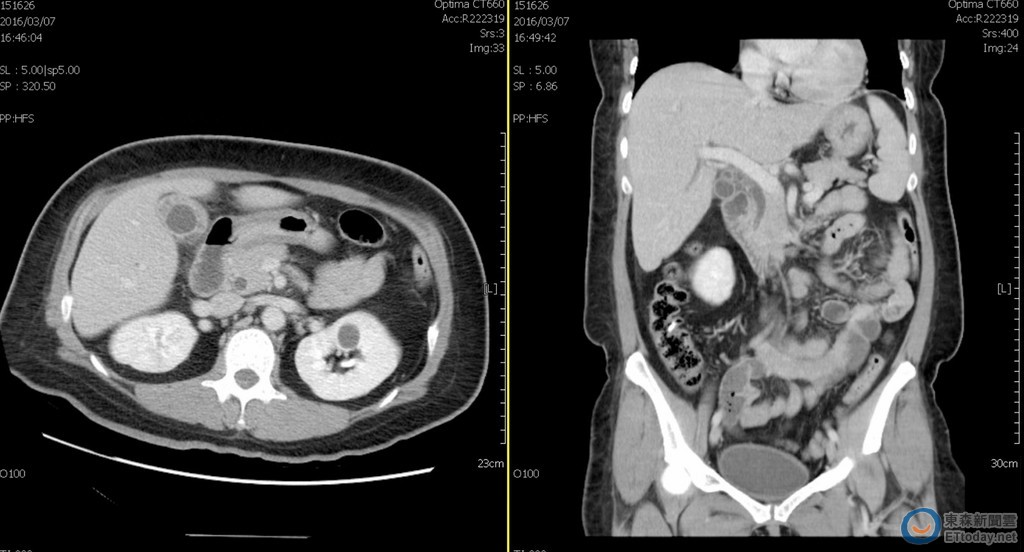

▲電腦斷層掃瞄,診斷遠端總膽管結石合併急性膽管及膽囊炎。(圖/安南醫院提供)

一名40歲女上班族,近日上妝照鏡子卻發現眼白及膚色略顯偏黃,如廁後更發現尿液偏深,近似烏龍茶的顏色,接下來食慾變差,發燒及右上腹劇痛的症狀,經台南市立安南醫院消化科曾邦豪醫師檢查,診斷遠端總膽管結石合併急性膽管及膽囊炎,經藥物治療與內視鏡取石手術後,目前於消化科門診追蹤中。